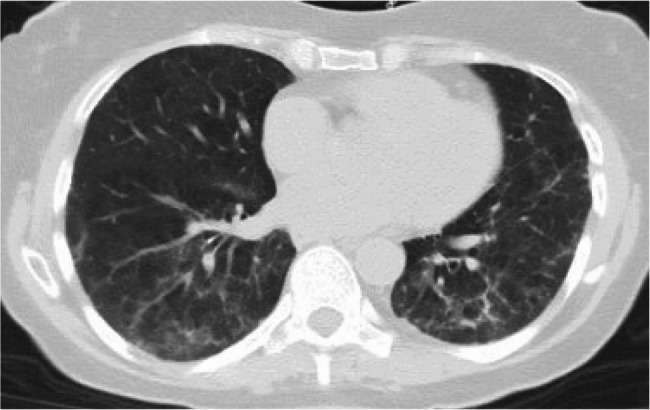

Case report: We discuss a 73-year-old woman with newly diagnosed DLBCL who underwent chemotherapy and immunotherapy with rituximab, cyclophosphamide, doxorubicin hydrochloride, vincristine sulphate, and prednisone (R-CHOP). Following her initial rituximab infusion, she developed shortness of breath, chills, rigors, flushing, and agitation. The rituximab infusion was paused, and hypersensitivity reaction medications were given per protocol. The infusion was resumed at a slower rate. Two weeks after initial infusion, she was hospitalized for shortness of breath and hypoxemia to 88% on pulse oximeter requiring 2 L of nasal cannula oxygen. Chest imaging showed new diffuse ground glass opacities (GGOs) on top of apical scarring, upper lobe emphysema, and few calcified granulomas. Patient underwent bronchoscopy for bronchoalveolar lavage (BAL) which was negative for infections and malignancy. Given the temporal relationship, chemotherapy induced lung injury was high on the differential, with rituximab being the possible offending agent. She was started on prednisone 60 milligram for 5 days with a follow up chest imaging showing resolution of the acute GGO. Her O2 requirements decreased from 3 L to 1 L and she was sent home with oxygen. Given the curative intent of R-CHOP, after shared decision making with the patient and her medical team, a treatment plan with a longer course of high and low prednisone was incorporated as part of her chemotherapy session. She was able to successfully finish her treatment with no additional episode, at which point she was able to be successfully tapered off her prednisone.